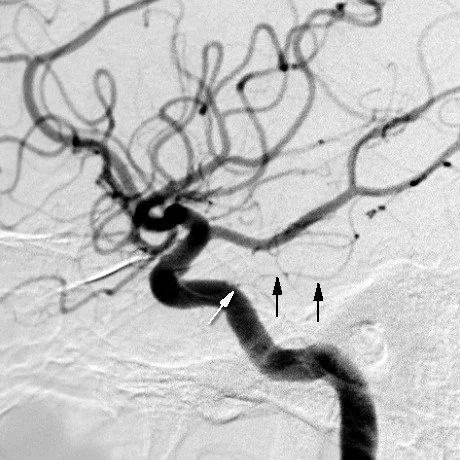

• Gives off Meningohypophyseal trunk (black and white arrows in angio below)

• Supplies hypophyseal trunk